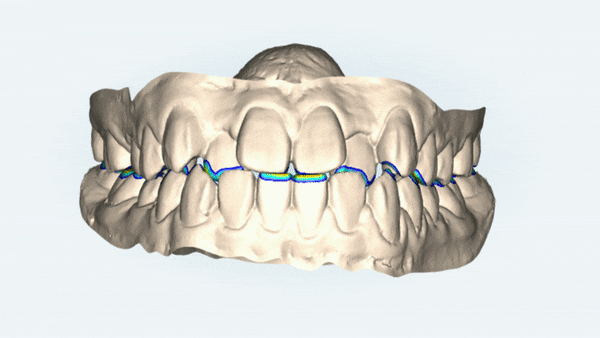

교정 진단을 위해 구내 사진을 찍어보았는데요

두번째 아래 앞니가 윗니를 덮고 있어 반대교합이 있을뿐만 아니라

앞니끼리 맞닿고 있어 치아가 마모되거나 치아끼리 힘을 받아 치은퇴축도 생길 수 있어

올바른 교합관계를 위해서 교정치료가 시급한 상황이었습니다.

악궁확장을 통해 비발치로 교정이 마무리된 모습입니다.

위 아래의 치아가 정상적인 교합이 되었을때 음식을 씹거나 발음을 하는데 적절한 기능을 갖게 됩니다.

정상적인 교합이 이루어지지 않으면 그만큼 치아의 기능이 떨어지게 되는데

교정 후 반대교합이 개선되고, 치아끼리 맞닿는 부분도 제자리를 찾아 올바른 교합관계로 개선되었습니다.